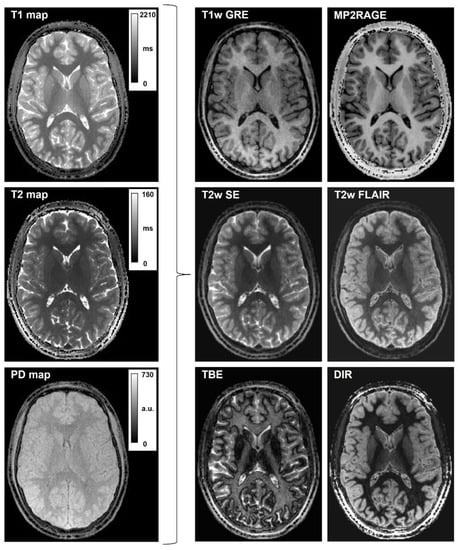

- Synthetic T1-weighted images simulating GRE (Gradient-recalled Echo) were synthesized with the following equation, incorporating the input maps of PD and T1 and setting the simulated acquisition parameter TR:

- Bias-free T1-weighted MPRAGE was synthesized by taking into consideration that B1 bias in QTI is incorporated in the PD map, which can be excluded from the formula, achieving a similar appearance to MP2RAGE uniform imaging [15]:

- Synthetic T2-weighted images simulating a SE (Spin Echo) acquisition were obtained as follows:

- Synthetic T2-FLAIR was obtained with a user-modified formula incorporating a coefficient TSAT, which enables the introduction of T1-weighting, which better mimics the one in conventional imaging:

- Synthetic TBE acquisitions were obtained from the generic signal model, with the appropriate parameters TI, TR, TE: